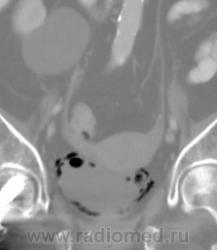

О чём могут говорить такие "газовые структуры" в области мочевого пузыря?

Наличие газа в мочевом пузыре может говорить о многом. Например стоял катетр Фолея, состояние после цистоскопии, эмфизематозный цистит, наличие фистулы.

А, чем именно, будет характеризоваться эмфизематозный цистит? При нем "пузырьки газа" локализуются в слизистой оболочке или где?

В просвете, может быть и в самой стенке. Смотрите здесь:

процесс в стенке в данном случае.

У женщины киста правой почки, подозрение на жировой гепатоз, стержень в головке и шейке правого бедра (остеосинтез). А про воздух возле/в стенке мочевого пузыря... не было ли оперативного вмешательства в малом тазу? И без аксиальных срезов явно я бы не сказала, где конкретно воздухblush...

Фик с ней с кистой... И какая разница аксиалы и короналы... Да, толстоваты срезы, эффект усреднения. Но я бы думал в сторону язвенного/гангренозного цистита (эмфизематозного цистита). Естественно, анамнез и клиника и всё встанет на свои места. На состояние после катерера не очень похоже...